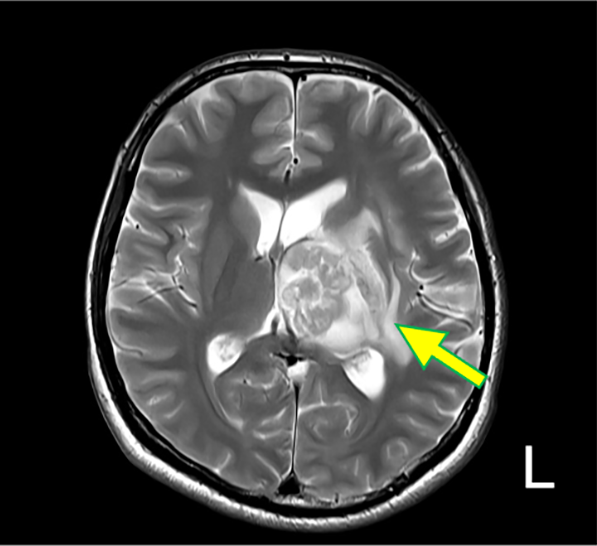

図2.T2WI (Tra.)

比較的整な辺縁を持つ嚢胞の内部に、不整形の実質構造を認める(矢印)。第3脳室は圧排され閉鎖している。周辺浮腫を伴っている。